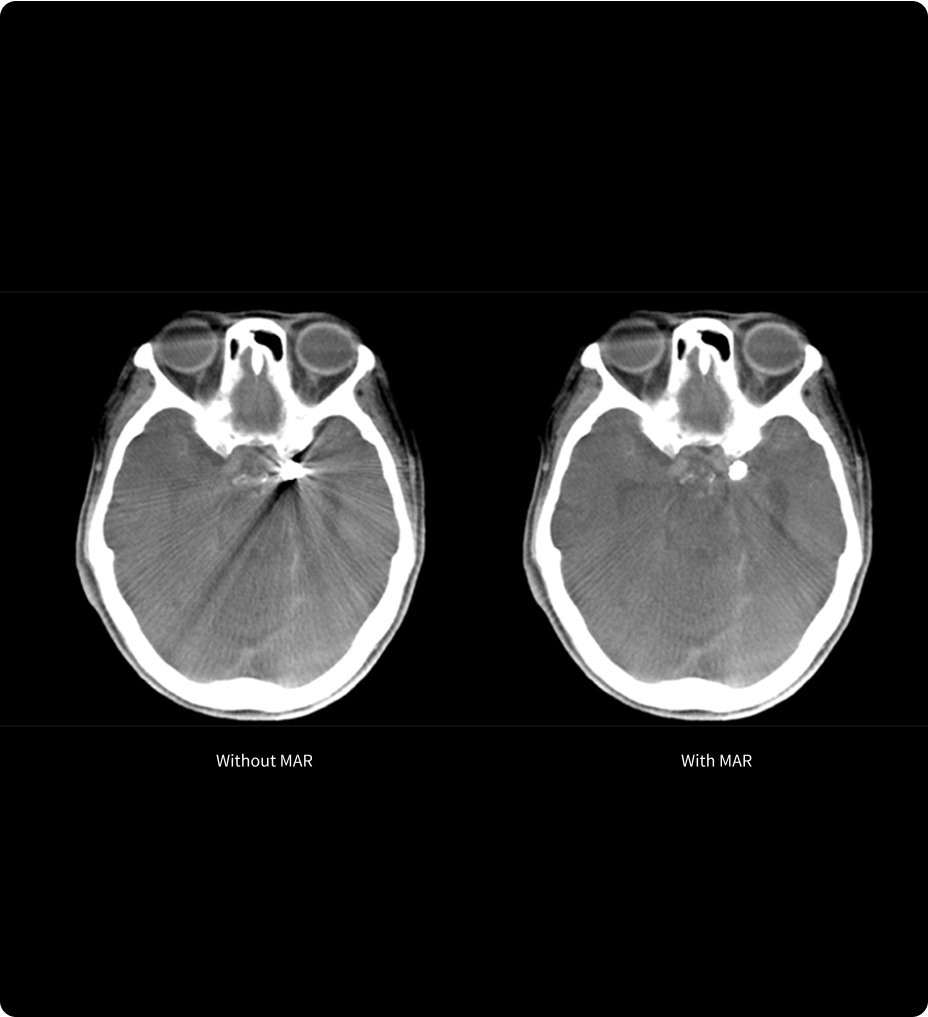

TrueFidelity DL + True Enhance DL

Better together

With the Revolution Ascend Platform, you can combine both of our AI-based imaging reconstruction technologies to create one stunning image. By combining True Enhance DL with TrueFidelity DL, you can achieve images that have less noise, enhanced sharpness and better noise texture than images obtained with ASiR-V.